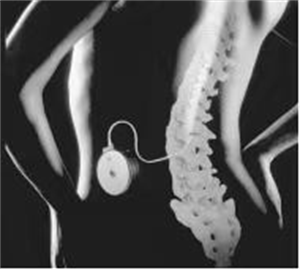

鞘内吗啡泵植入术是一种植入式的给药装置,在手术过程中将导管放入蛛网膜下腔内,通过根导管把微量的药物直接送到疼痛中枢,不经过胃肠道,不经过肝肾,它的用量会比吃药要小的多.这样减少了口服大量镇痛药物的副作用,又能减少患者不良反应及并发症的发生。

鞘内吗啡泵植入术要求医生在进行手术的过程中精准的定位疼痛部位以及脊髓节段,属于微创介入手术,开一个两三公分的小孔把给药装置植入进去。它适用于癌性疼痛(恶性肿瘤肿瘤性疼痛)和非癌性疼痛(弥散性疼痛、腰背部手术失败综合征、轴性躯干性疼痛、严重骨质疏松症、蛛网膜炎、内脏性疼痛、头部/颈部疼痛、痛性神经病、脊髓损伤、幻肢痛、带状疱疹后疼痛、复杂性局灶性疼痛综合征(CRPS)等),它能有效控制患疼痛,减少副作用,提高患者的生活质量。